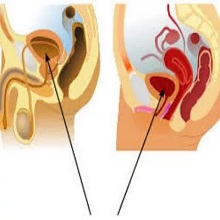

| Бенигна хиперплазија простате (БХП) представља немалигно увећање простате, које се често јавља код мушкараца старијих од 50 година. Ово стање се сматра физиолошким и обично није проблематично све док не доведе до симптома који утичу на квалитет живота пацијента. |

| Еректилна дисфункција представља болест данашњице, о којој се још увек мало прича, а са медицинске стране много зна. Јавност још увек не даје много пажње овој болести/стању. Према дефиницији уролошке Европске асосијације, то је стање где долази до трајне немогућности постизања ерекције, да би задовољила сексуалну функцију. Дели се на минималну, умерену и комплетну. |